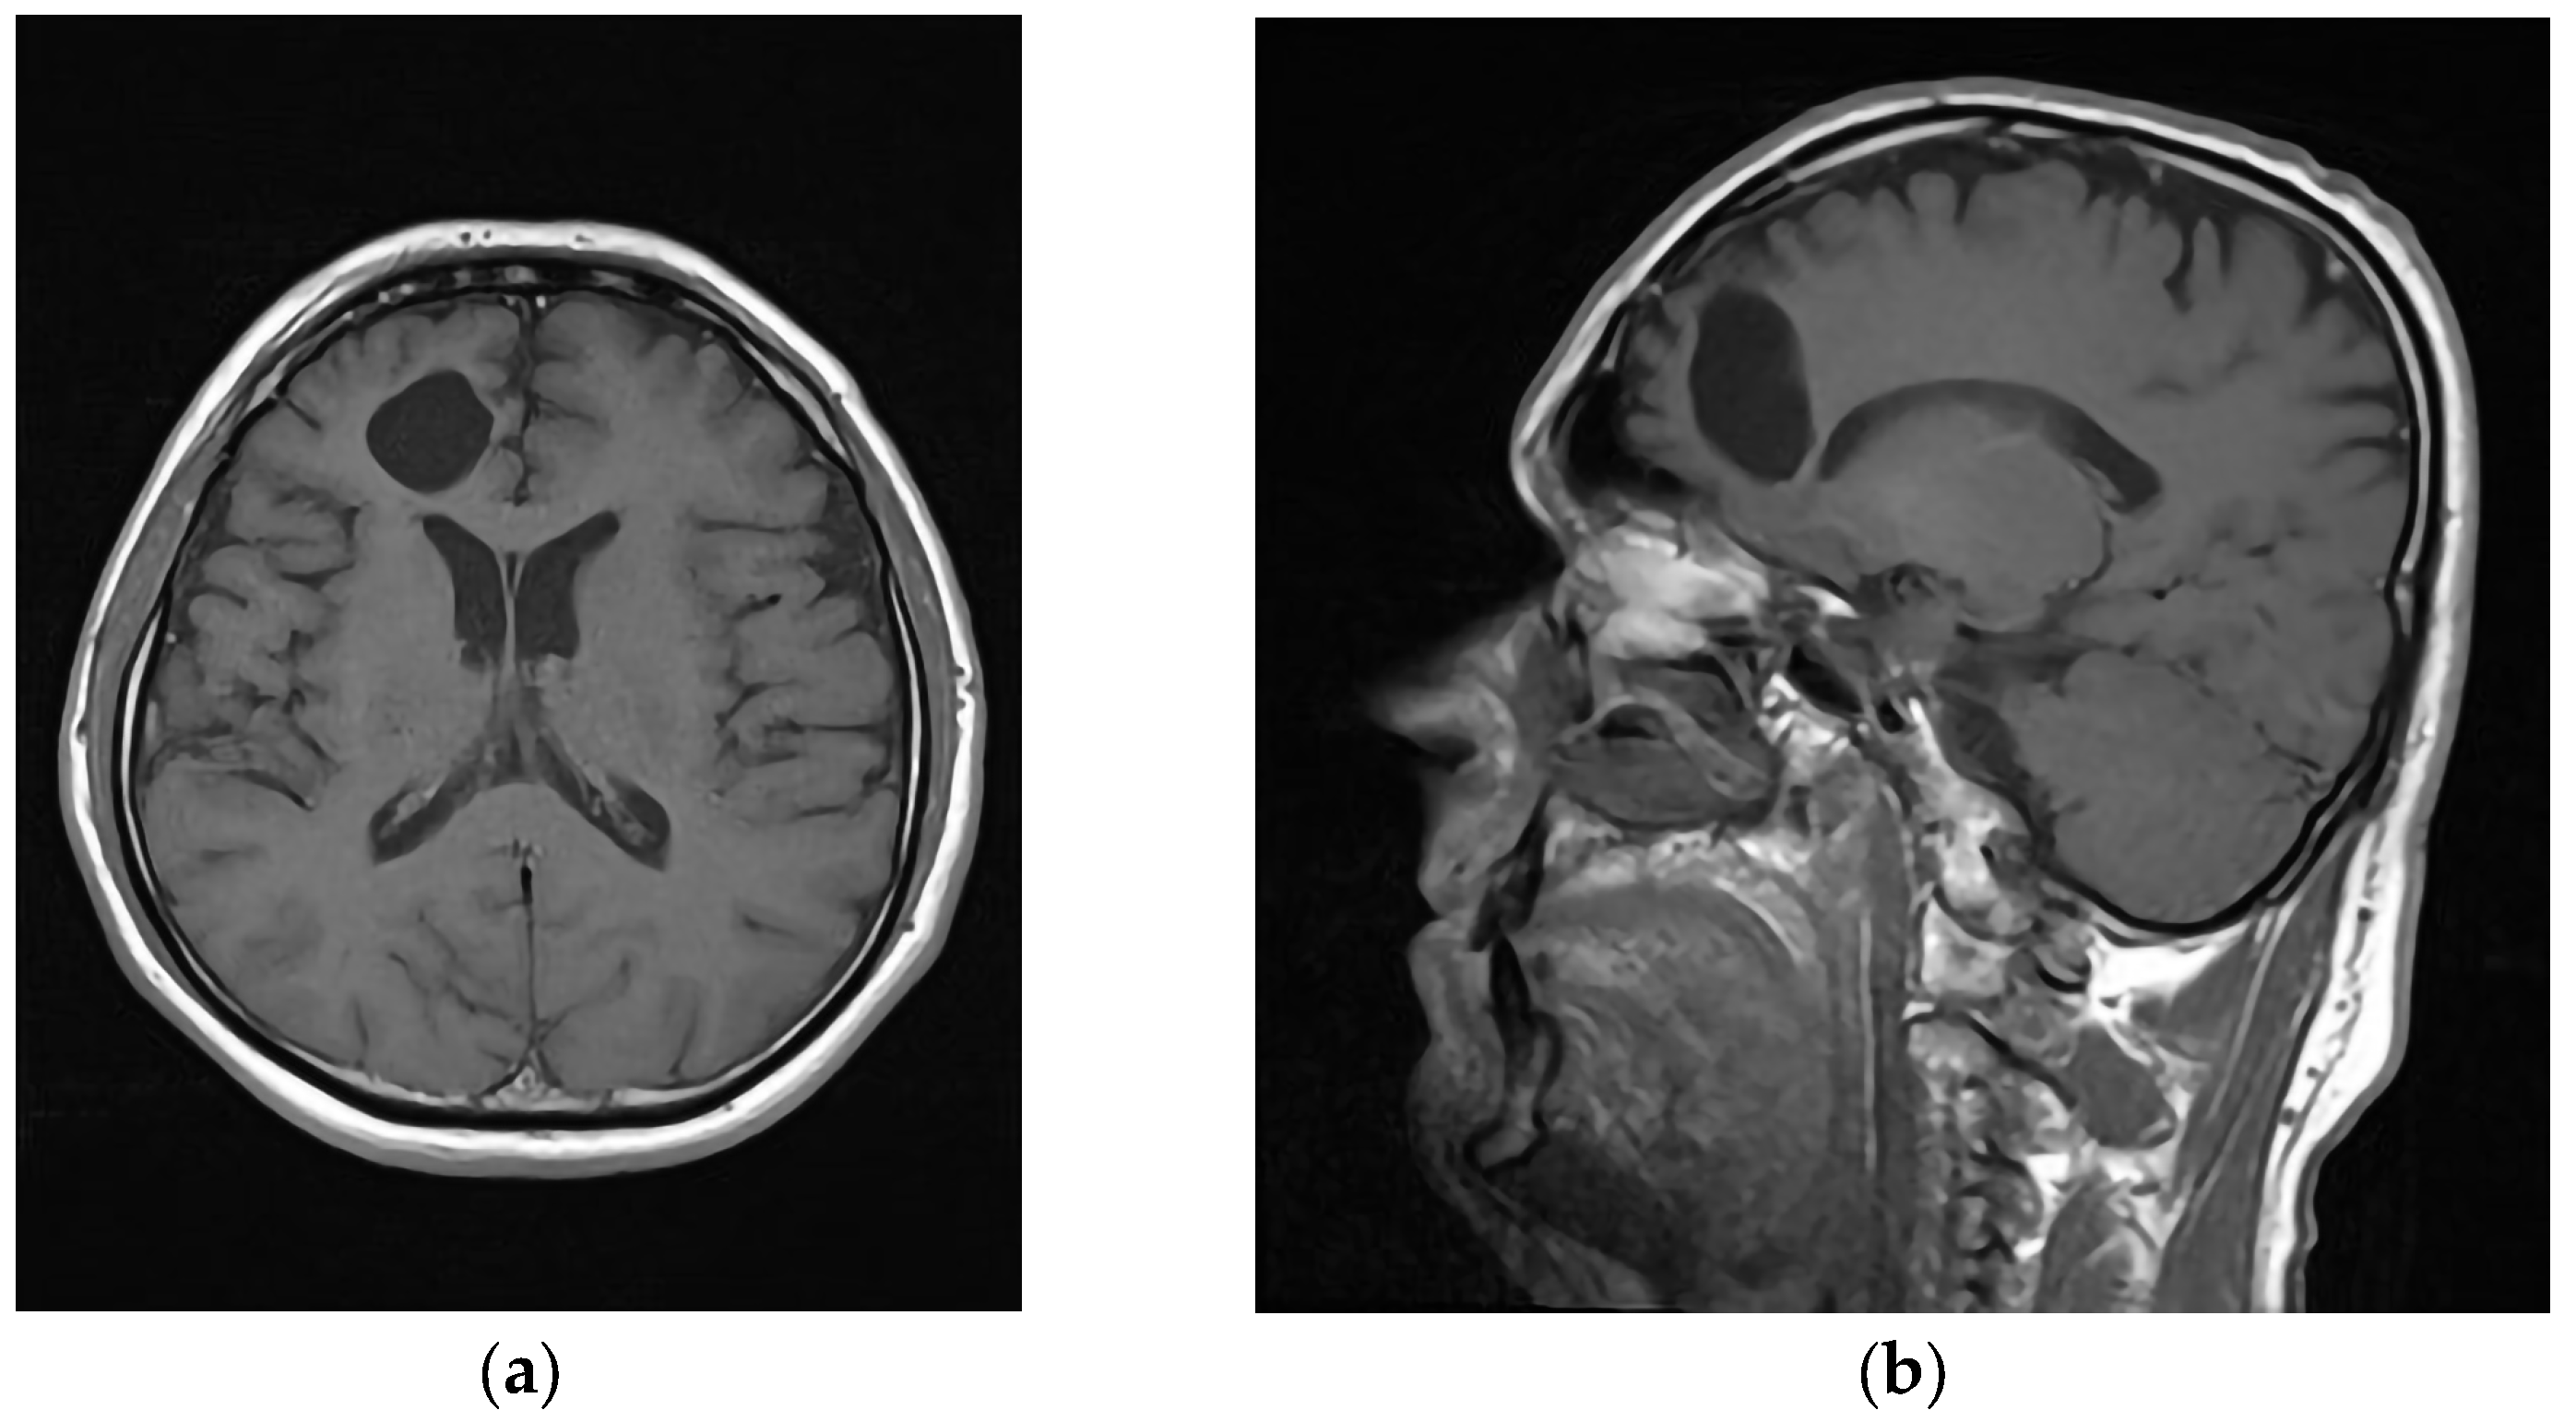

To investigate the underlying cause of the patient’s symptoms, magnetic resonance imaging (MRI) was performed using Siemens Magnetom Avanto 1.5 T in Erlangen, Germany. The MRI scan revealed a significant abnormality in the right frontal lobe, depicted in Figure 1a,b. Figure 1a displayed the presence of an abscess within the right frontal lobe. Additionally, periabscess edema and displacement of midline structures were evident, indicating compression of the surrounding tissue. Figure 1b illustrates the abscess attached to the orbital roof, and the trajectory of the injury from approximately one month earlier. The foreign body’s trajectory, which penetrated the upper part of the upper eyelid conjunctival region, followed a periosteal path along the orbital roof, ultimately reaching the posterior part of the orbital roof within the frontal lobe region, as shown in Figure 1c. An ophthalmologist confirmed the diagnosis of orbital cellulitis, as depicted in Figure 1d.

Figure 1.

Preoperative MRI; (a) axial T2W slice with abscess in right frontal lobe (red arrow) and perifocal edema (*); (b) sagittal T1W slice with attachment of abscess to roof of orbit (red arrow); (c) coronal T1W slice with position of brain abscess and roof penetration (red arrow); (d) coronal T1W slice with intraorbital infective process presence (red arrow).